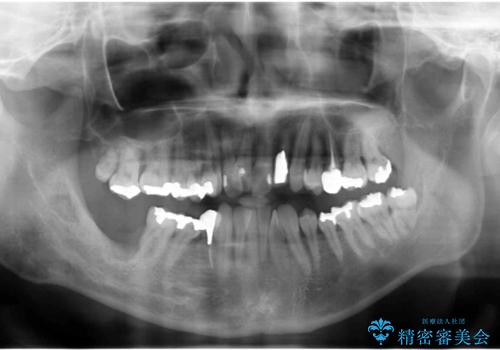

- 歯周病を気にして来院。

前歯の虫歯を治そうにも、歯並びの問題で難しい状態でした。

右下の奥歯も欠損しており、インプラント治療が必要な状態でした。

前歯の部分矯正を行い受け口を改善しました。

奥歯まで動かそうとすると顎の手術の適応になってしまうため、奥歯はそのままにして前歯のかみ合わせを改善しました。

また、奥歯はインプラント治療を行い、矯正で下の前歯を後ろに下げるのに使用しています。

前歯が重なっているところの虫歯治療が難しく、そこから矯正治療の提案となりました。

下の前歯1本、また、左上2番を保存不可能なため抜歯しています。

通常骨格的な受け口を部分矯正でというのは不可能なことが多いのですが、今回はいろいろな条件が重ねなりお引き受け可能でした。通常は難しいです。